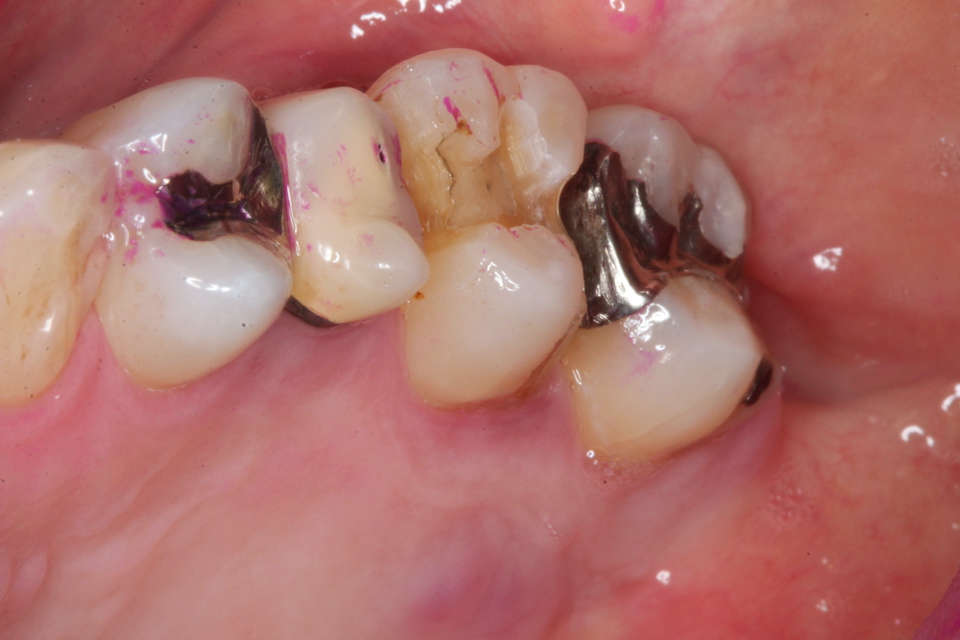

ブリッジ脱離で2次カリエス+Perでグラグ… 2025.11.01

ブリッジ脱離で2次カリエス+Perでグラグ… 2025.10.31